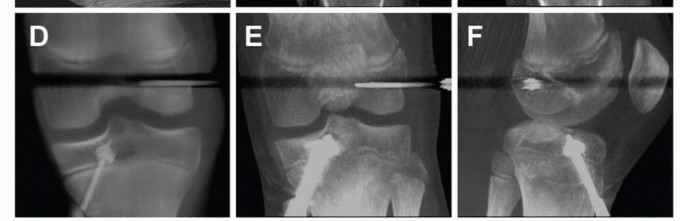

Graft Passage and Fixation

The passing sutures on the cortical button device are placed in the loop of the Nitinol wire and pulled through the tibial tunnel, through the femoral tunnel, and out the lateral thigh ( TECH FIG 7A ).

The cortical button is passed just to the femoral cortex and flipped ( TECH FIG 7B ). Then, the graft is cinched up to the button until fully seated in the femoral tunnel.

Alternatively, the cortical button is passed through the lateral femoral cortex until the graft is fully seated in the femoral tunnel. Then, the cortical button is cinched down to the lateral femoral cortex.

Fixation of the self-cinching mechanism can be reinforced by a couple of overhand knots tied over the button.

Tension is applied to each limb of the graft to ensure that there is even tension in all strands and no graft slippage.

The knee is then extended to ensure that there is no graft impingement and cycled about 10 to 20 times with tension applied to the graft.

The knee is flexed to 20 to 30 degrees, tension is applied to the graft, and a posterior drawer force placed on the tibia.

On the tibial side, the graft is fixed either with a soft tissue interference screw if there is adequate tunnel distance (at least 30 mm) below the physis to ensure metaphyseal placement of the screw ( TECH FIG 7C ) or with a post and spiked washer ( TECH FIG 7D ).

Fluoroscopy can be used to ensure that the fixation is away from the physis if there is any question. -

TECH FIG 7 • Graft passage and fixation for transphyseal reconstruction with metaphyseal fixation. A. The Nitinol wire is used to pass the cortical button device and graft through the tibial tunnel and into the femoral tunnel. B. The cortical button is flipped and seats perpendicular to the cortex. C. Tibial fixation is with an interference screw if enough graft and tunnel length is present inferior to the proximal tibial physis. D. Alternatively, a post and spiked washer may be used.